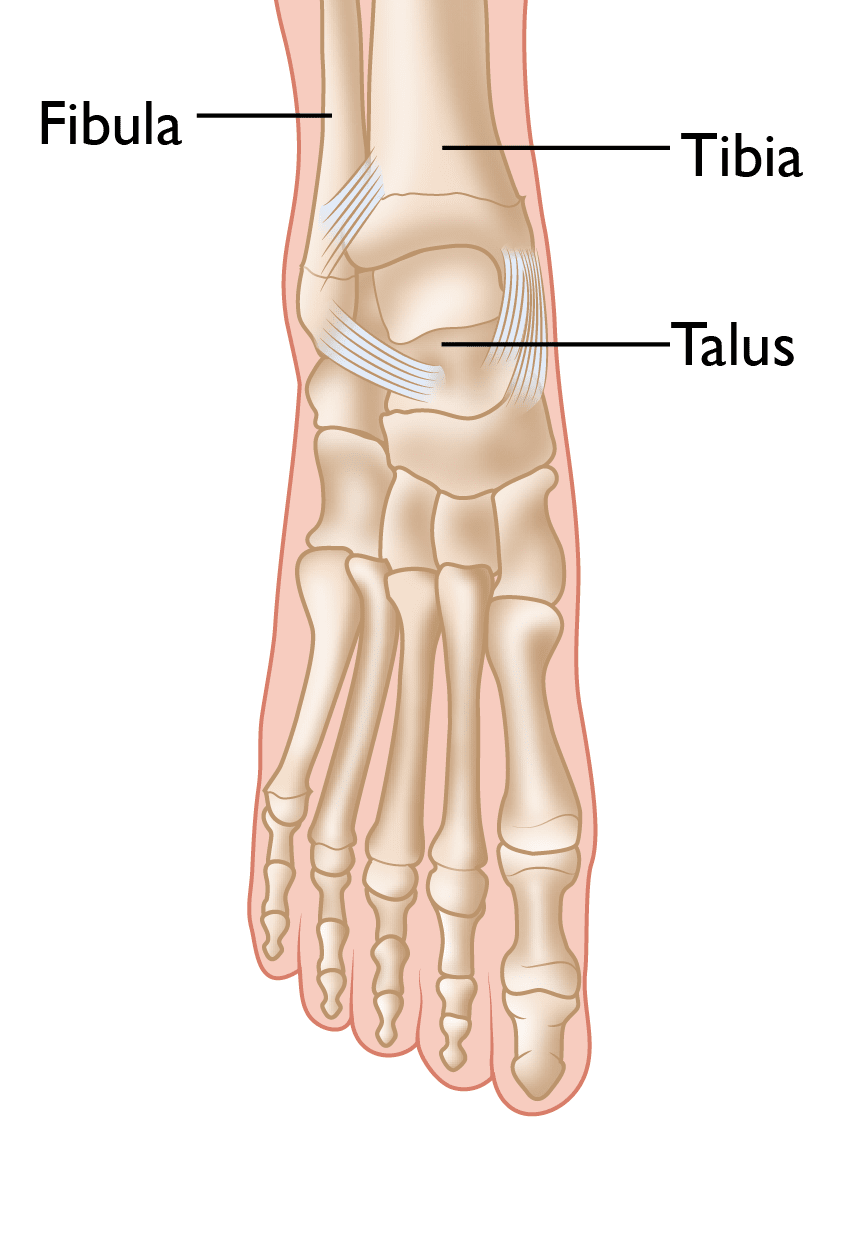

The location where the tibia, fibula, and talus bones come together is called the ankle joint.

Bones are connected to other bones by ligaments, which act like strong ropes to hold the bones together. The ankle has several ligaments that help keep the ankle joint stable.

normal foot anatomy

The normal skeletal anatomy of the foot and ankle.

Reproduced and modified with permission from The Body Almanac. © American Academy of Orthopaedic Surgeons, 2003.